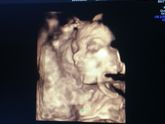

Наши 23 недельки. Лицом уткнулась в плаценту,закрывалась ручками,открывала ротик. Гиперплазия плаценты на ребёночка никак не влияет))) пока что тазовое предлежание. Пока что всё хорошо(ттт)